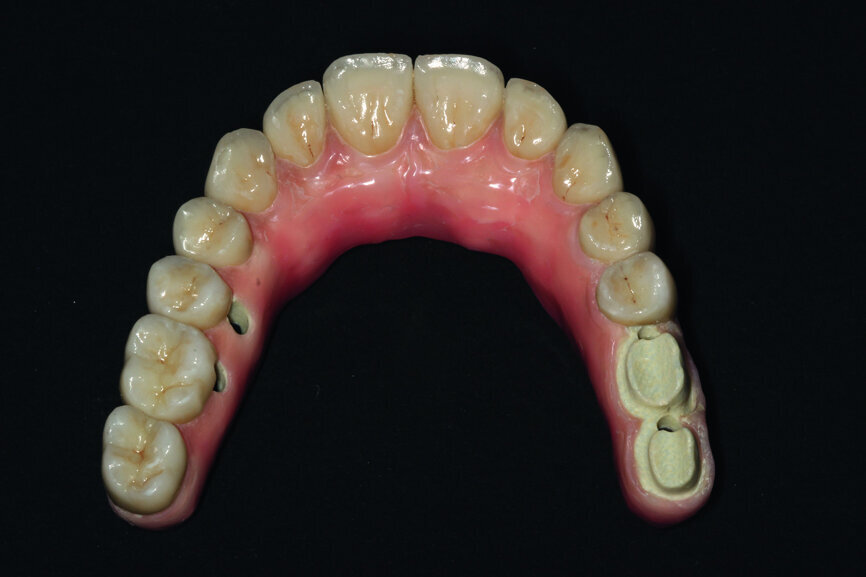

Fig. 20: Prosthetic work based on a model where veneering of the gum was started and with crowns.

Fig. 21: Openings for screws are located before placing the crowns.

Fig. 22: Comparison of the pattern, that is, the temporary prosthesis and the final prosthetic work.

Fig. 23: Final restoration prior to handover and the placing of crowns.

After the test, we sent the construction to a prosthetic laboratory with detailed guidelines for veneering. To achieve the proper location of the pink veneering it was necessary to place the porcelain crowns onto the bar and model the border line for the gingival garland (Figs. 18–20). Due to the fact that the prosthesis constituted the ideal shape of the teeth, it was worth comparing it with the final prosthetic work and assessing the details of the whole work process before the patient sits comfortably in the dental chair (Figs. 21–25).